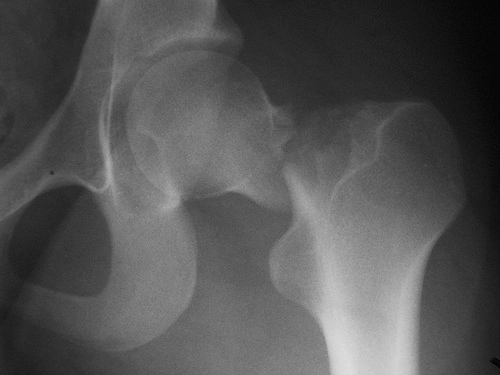

Un estudio halló que más del 75% de los pacientes fracturados recibían fármacos que aumentan el riesgo de fractura. Además, la mayoría los siguió utilizando después. JAMA Internal Medicine, 22 de agosto de 2016